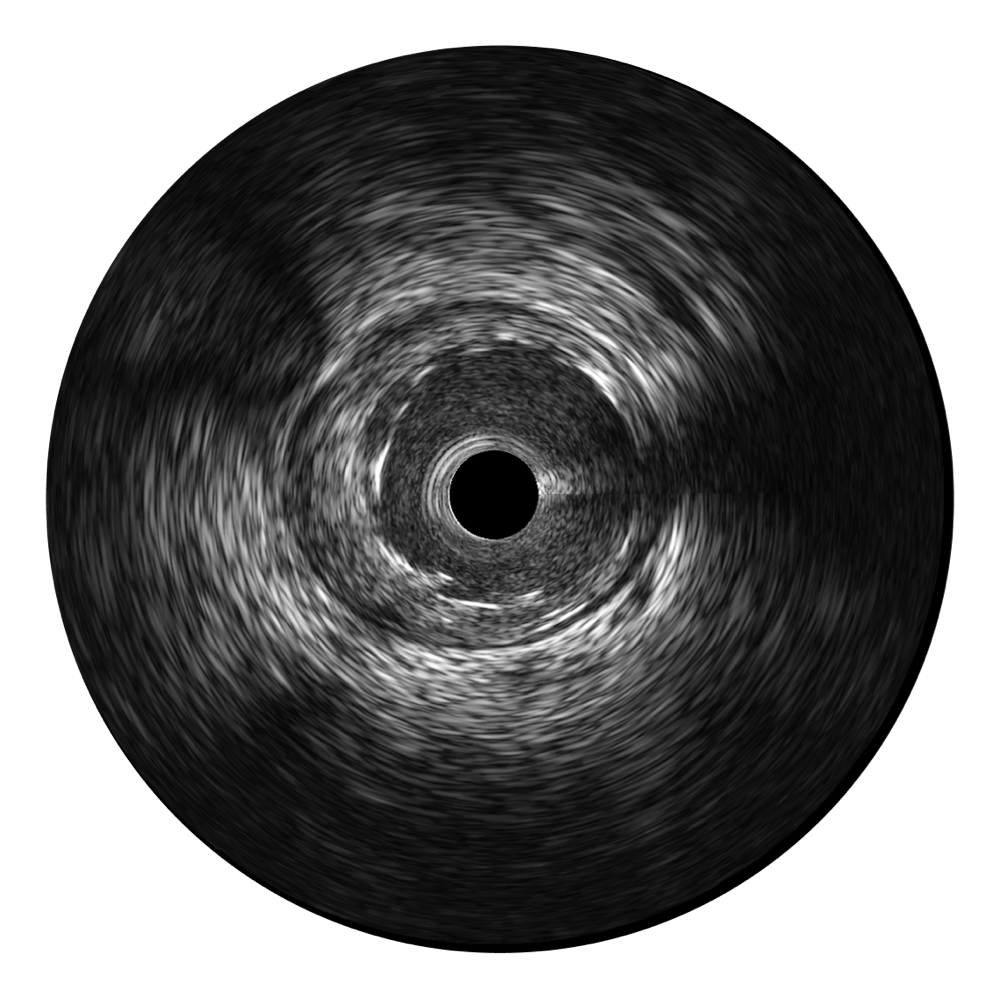

開(kāi)立超寬頻成像技術(shù)覆蓋20-80MHz1或20-90MHz2頻率范圍, 提供優(yōu)異的分辨力同時(shí)也保證充足的穿透深度

對(duì)比傳統(tǒng)IVUS導(dǎo)管成像,開(kāi)立寬頻IVUS圖像的近場(chǎng)支架梁顯影更細(xì)膩,遠(yuǎn)場(chǎng)中膜外血管仍清晰可辨,兼顧遠(yuǎn)中近,兼顧分辨力與穿透深度